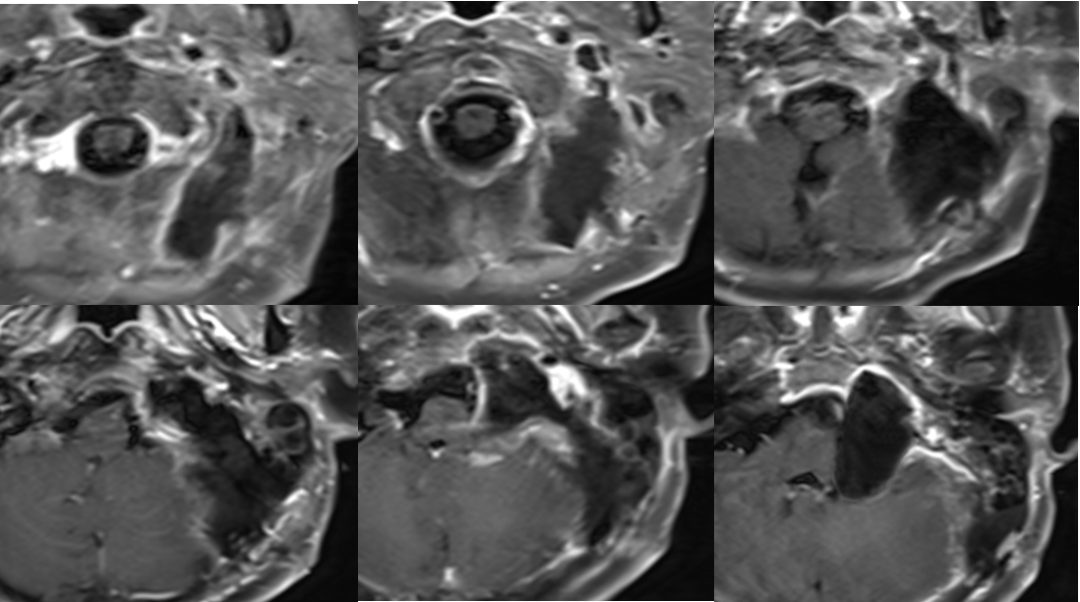

术前影像

![]()